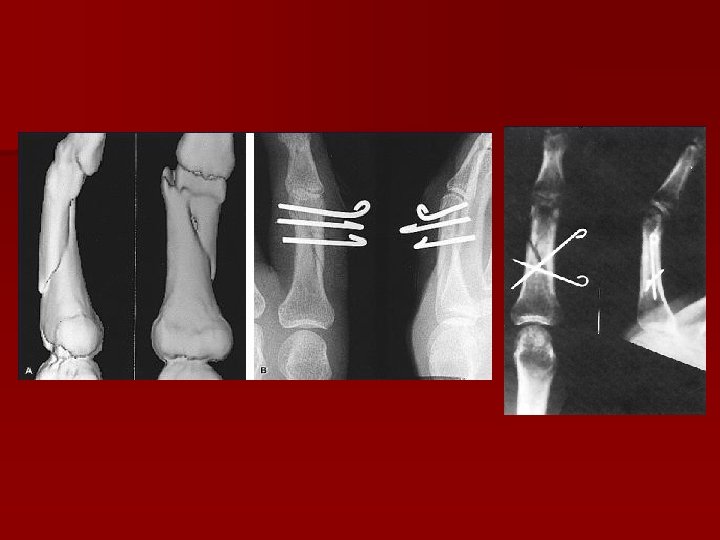

OS placă- şuruburi